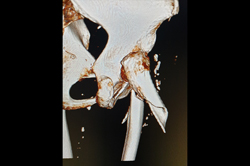

Distal Femur

Periprosthetic Fracture THR

Proximal Tibia